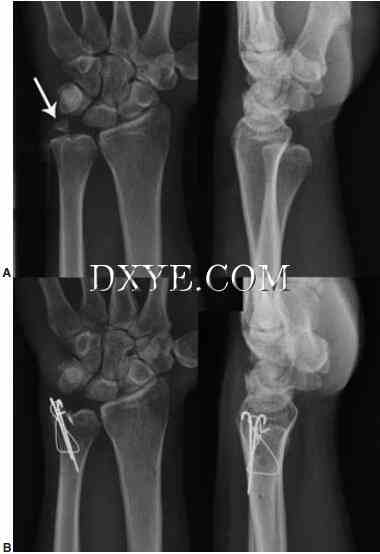

尺骨茎突骨折。 超过50%的桡骨远端骨折伴有尺骨茎突骨折,但并非所有的尺骨茎突骨折均需要修复。 手术干预取决于DRUJ的稳定性。 发现尺骨茎突基底骨折和位移大于2 mm的基底骨折会影响DRUJ的稳定性。 当根据放射照片的外观怀疑DRUJ不稳定时,对照正常的手腕检查DRUJ在中性,完全旋后和完全旋前的平移松弛。 一旦桡骨远端骨折已经修复,外科医生应该检查受伤的手腕并将其与正常侧进行比较。 如果DRUJ松弛,尤其是完全旋后,尺骨茎突修复。 可以使用克氏线,张紧带线或空心无头螺钉(图76.18)。 使用糖钳或Munster型夹板,将前臂在中性旋转下固定4至6周。

18.jpg

图 76.18.  延迟与尺骨茎突骨折不愈合DRUJ不稳定表现。A.术前X线片显示桡骨相对尺骨背侧半脱位,与尺骨茎突显示箭头移位。B.晚期术后X线片显示尺骨茎突与TFCC重新插入使用骨锚钢丝张力带。